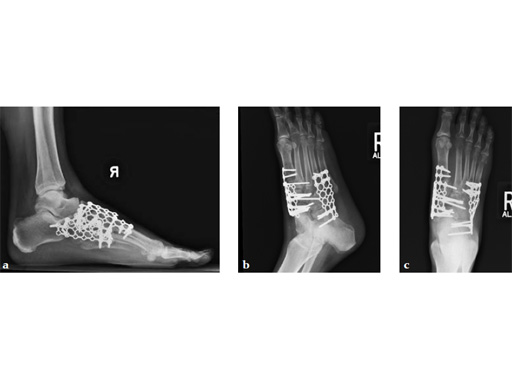

Case 5: First TMT, straight fusion and TMT fusion plates

A 46-year-old obese woman with coronary artery disease had sustained a Lisfranc injury while performing an exercise program. She was unable to weight bear and used an electric scooter.

In an effort to restore her ability to exercise and taking into consideration her body weight and upper extremity weakness, a decision was made to use the variable angle locking compression plate. These postoperative x-rays were obtained at 3 months, one month after beginning weight bearing. The patients pain was reduced and she was able to resume a progressive exercise program after 4 months following surgery.

Case provided by Michael Castro, Scottsdale, Arizona